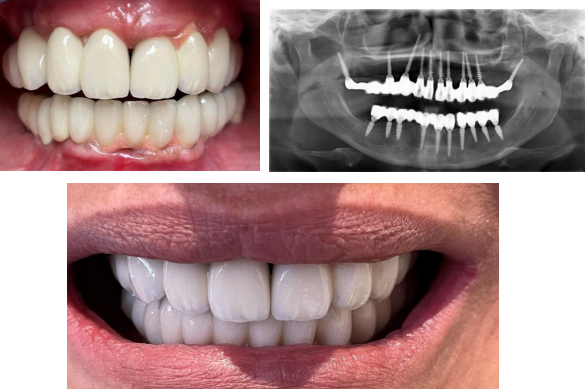

Figure 5: Clinical photograph and the panoramic radiograph of patient and after bridge delivery, day of placement

The patient, a lady of 56 years old came to clinic with periodontal problems, she desired a solution and oral rehabilitation in a minimal invasive way.

After intra oral examination and radiological reviews (panoramic radiograph and cone beam computer tomography scan) It was observed that the width and height of alveolar bone is not enough for classic implant placement, as a result the choice of appropriate implant is important fig 6.

With bone width of 5 to 6 mm One piece Tissue level implants (ROOTT, TRATE AG) were the implants of choice.

Figure 6